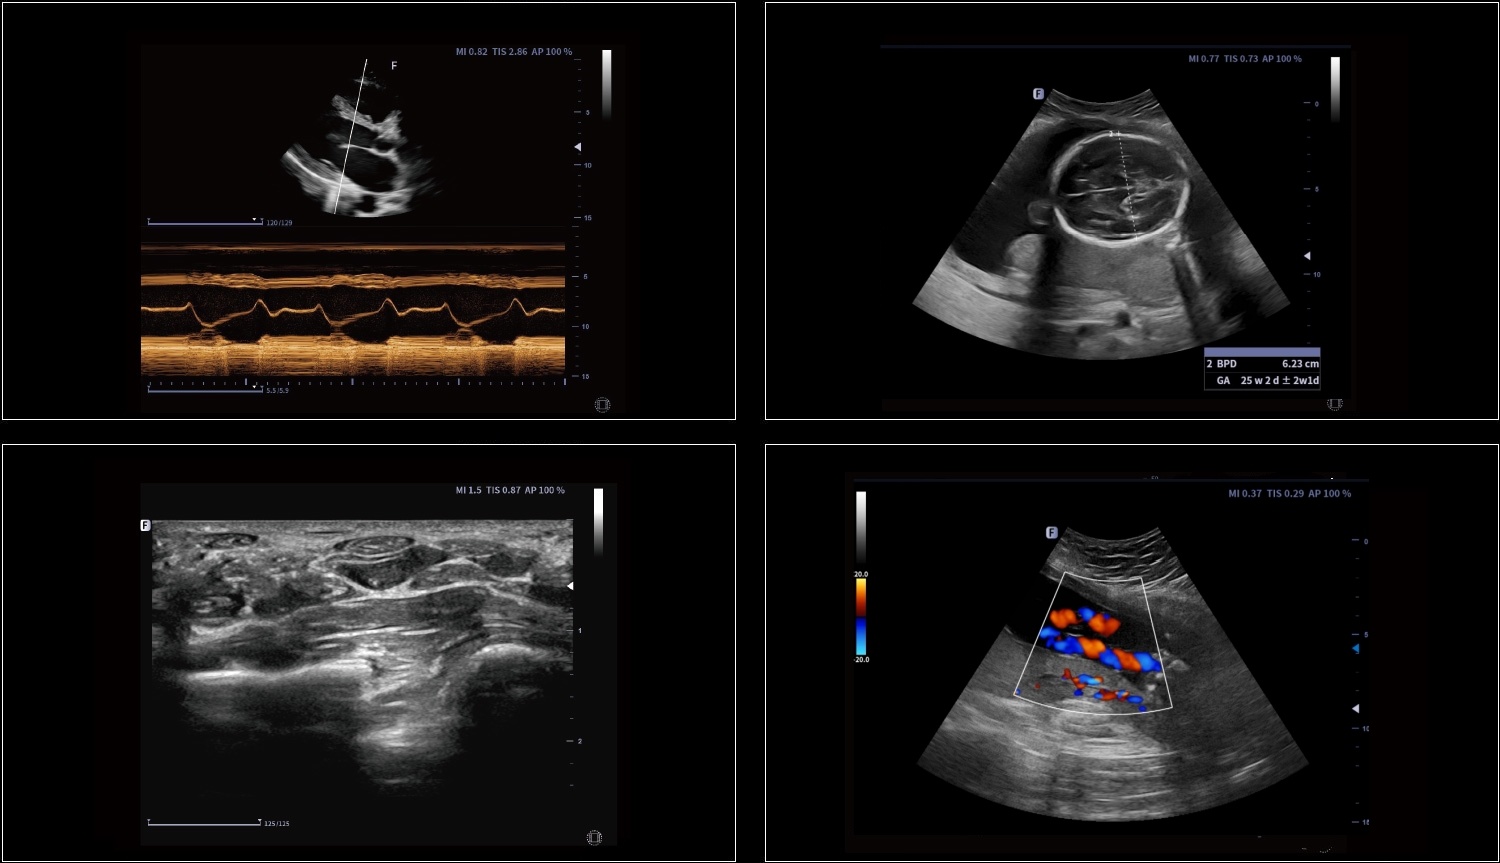

Rozszerzone pole widzenia wyświetla więcej informacji obrazowych bez utraty jakości obrazu. Jest wygodnym podejściem do dużych organów, zwłaszcza struktur układu mięśniowo-szkieletowego. Posiada wskazania dotyczące kierunku i prędkości skanowania.

Elastografia w czasie rzeczywistym to nowa nieinwazyjna i bezbolesna technika, która pomaga określić twardość organów oraz innych struktur takich jak piersi czy tarczyca. Obrazowanie elastyczne dostarcza użytkownikom dynamicznych informacji wizualnych i pokazuje sztywność organów, co jest pomocne w bezpośredniej i ilościowej diagnozie oraz leczeniu.

Zastosowania: Małe części,

Naczyniowe, MSK